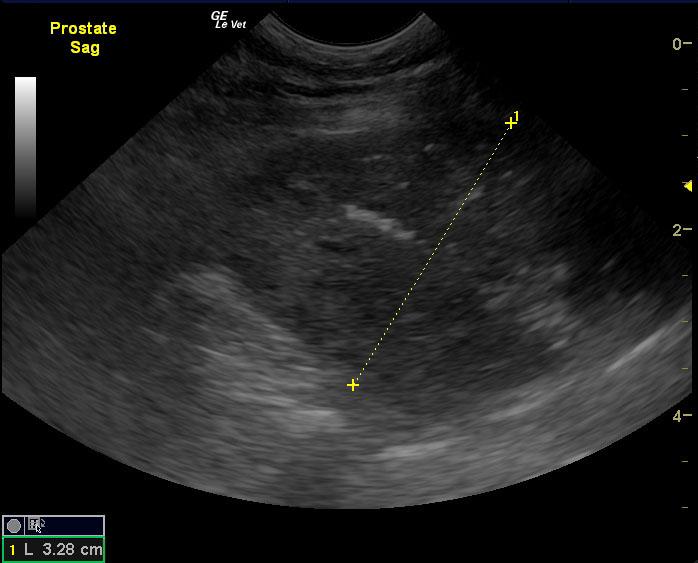

A 9-year-old NM canine mix was presented for evaluation of hematuria and urinating in the house that has not responded to a course of Baytril. Red and white blood cells were evident on urinalysis.